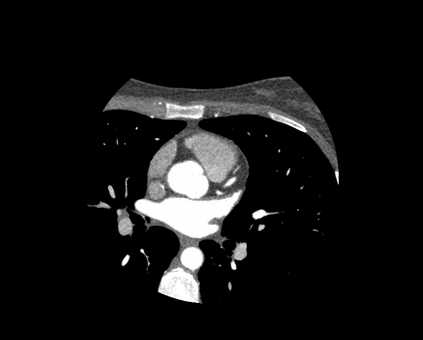

The standard non-invasive imaging technique used to assess the severity and extent of Coronary Artery Disease (CAD) is Coronary Computed Tomography Angiography (CCTA). However, manual grading of each patient's CCTA according to the CAD-Reporting and Data System (CAD-RADS) scoring is time-consuming and operator-dependent, especially in borderline cases. This work proposes a fully automated, and visually explainable, deep learning pipeline to be used as a decision support system for the CAD screening procedure. The pipeline performs two classification tasks: firstly, identifying patients who require further clinical investigations and secondly, classifying patients into subgroups based on the degree of stenosis, according to commonly used CAD-RADS thresholds. The pipeline pre-processes multiplanar projections of the coronary arteries, extracted from the original CCTAs, and classifies them using a fine-tuned Multi-Axis Vision Transformer architecture. With the aim of emulating the current clinical practice, the model is trained to assign a per-patient score by stacking the bi-dimensional longitudinal cross-sections of the three main coronary arteries along channel dimension. Furthermore, it generates visually interpretable maps to assess the reliability of the predictions. When run on a database of 1873 three-channel images of 253 patients collected at the Monzino Cardiology Center in Milan, the pipeline obtained an AUC of 0.87 and 0.93 for the two classification tasks, respectively. According to our knowledge, this is the first model trained to assign CAD-RADS scores learning solely from patient scores and not requiring finer imaging annotation steps that are not part of the clinical routine.